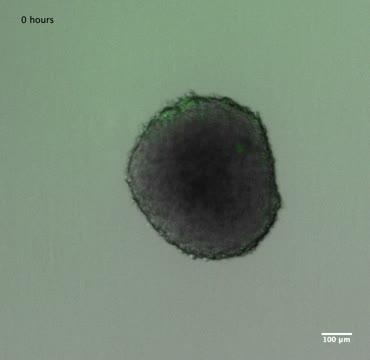

video: Engineered bacteria (green) invade a tumor spheroid in a dish.

Tetsuhiro Harimoto/Columbia Engineering

Researchers at Columbia Engineering report today in PNAS that they have developed a system that enables them to study tens to hundreds of programmed bacteria within mini-tissues in a dish, condensing the time of study from months to days. As a proof of concept, they focused on testing programmed antitumor bacteria using mini-tumors called tumor spheroids. The speed and high throughput of their technology, which they call BSCC for "bacteria spheroids co-culture," allows for stable growth of bacteria within tumor spheroids enabling long-term study. The method can also be used for other bacteria species and cell types. The team, led by Tal Danino, assistant professor of biomedical engineering, says that, to their knowledge, this study is the first to rapidly screen and characterize bacteria therapies in vitro and will be a useful tool for many researchers in the field.

"We used 3D multicellular spheroids because they recapitulate conditions found in the human body, such as oxygen and nutrient gradients--these can't be made in a traditional 2D monolayer cell culture," says the paper's lead author Tetsuhiro Harimoto, who is a PhD student in Danino's lab. "In addition, the 3D spheroid provides bacteria with enough space to live in its core, in much the same way that bacteria colonize tumors in the body, also something we can't do in the 2D monolayer culture. Plus, it's simple to make large numbers of 3D spheroids and adapt them for high-throughput screening."